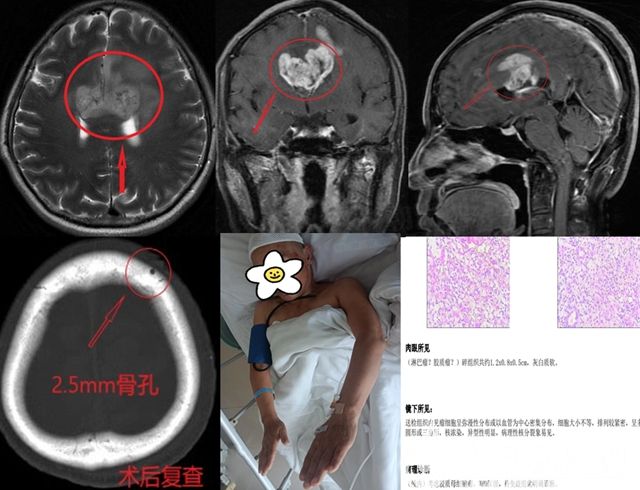

病例二:患者張某,無明顯誘因出現(xiàn)反應(yīng)遲鈍,伴右側(cè)肢體活動不靈,病情持續(xù)性進(jìn)展。行影像檢查提示,雙側(cè)胼胝體病變,淋巴瘤可能性最大,但不排除膠質(zhì)瘤可能。如病變?yōu)榱馨土?,則應(yīng)首選放化療治療;如為膠質(zhì)瘤,其惡性程度很高,且因病變位于雙側(cè)胼胝體,術(shù)后生活質(zhì)量不高,極易復(fù)發(fā)。經(jīng)神經(jīng)外二科醫(yī)療團(tuán)隊討論后,決定為患者實施機(jī)器人輔助腦穿刺活檢術(shù),最終明確病理診斷為膠質(zhì)母細(xì)胞瘤(WHO IV級)。